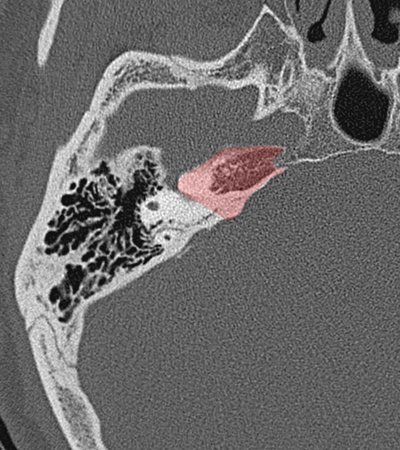

Temporal bone Petrous apex Sphenoido-temporal suture Occipitotemporal suture Petroclival suture

Radioanatomy of Temporal bone